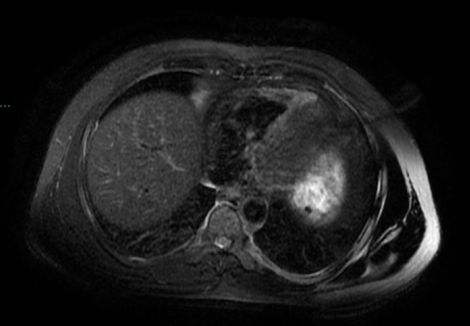

2023.01.14定期复查肝脏MRI:肝VIII段转移灶治疗后改变,未见复发征象。

2023. 04.26复查肝脏MRI:肝VIII段转移灶治疗后改变,未见复发征象。

目前,程先生仍在接受免疫维持治疗,密切随访。